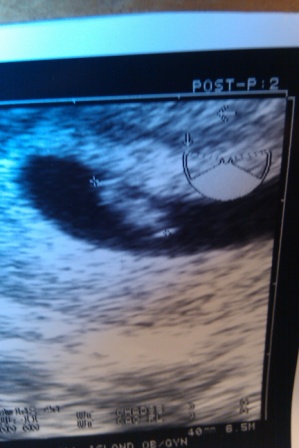

7W Appointment & EDD!

Well it's looking like we are having a singleton. The second sac is still there, but it didnt grow at all from last week and was def empty. I was a little sad but I am SO excited and grateful that we have one big healthy one. I guess that's why we transferred 2 embryos!! The heart rate was 127 which Dr. B said was fine. I am measuring EXACTLY what I expected based on my ER, which is 7w1d and I have an EDD of 7.1.11 Yay for summer babies!!

We are so excited!! Watching that flicker on the screen is so amazing

I attached my 6w1d and 7w1d sonos below for anyone that's interested. I asked Dr. B why the sac looks like a banana and he said "ask God" . Image Attachment(s):